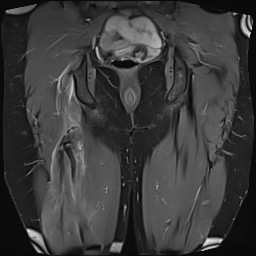

MRI

Proximal hamstring avulsion, with tendon floating in hematoma / seroma

Incomplete tears

High grade partial tear proximal hamstring